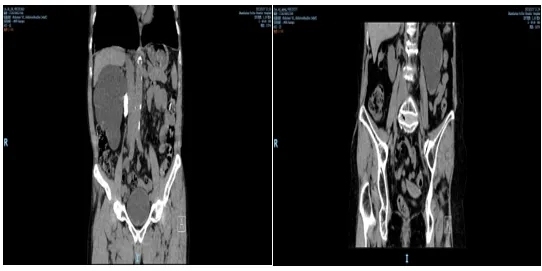

林先生(化姓)、左女士(化姓)均已年逾七旬。但近日,两人均因体检超声检查发现肾重度积水住院,泌尿系 CT 均提示:肾影明显增大,肾实质变薄、大部分呈细线状改变。

但不同的是,林先生受影响的是右肾,左女士的为左肾。造成这一严重后果的不是因为肾肿瘤,也不是因为严重的肾外伤,其罪魁祸首竟是“小小”的结石。

暨南大学附属顺德医院泌尿外科主任钟晓健带领科室团队对患者病情进行了仔细分析、研究:两位高龄患者肾重度积水,合并输尿管结石,且呈无功能肾表现;患侧肾脏体积已占据大半个腹腔,并向下延至盆腔,输尿管上段的结石引起肾门部位的反复炎症,将明显增加腹腔镜下游离肾蒂血管的困难和肾周组织器官损伤的风险,更何况是高龄患者。